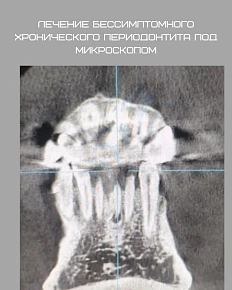

Зубосохраняющая реставрация